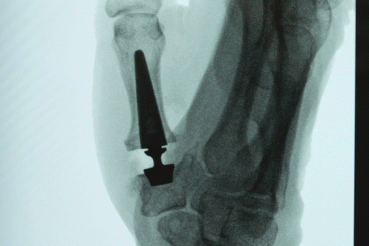

Bones and Joints Rush Offers First Thumb Joint Replacement in U.S. A new modular 3-part thumb joint replacement allows early return to strong and pain-free function